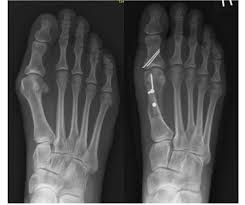

3.Fixação de fraturas (Osteossíntese)

É a cirurgia para alinhar e estabilizar fraturas ósseas com o uso de:

• Placas e parafusos

• Pinos e hastes intramedulares

• Fixadores externos

Indicada em fraturas com desvio, exposição ou que não ciclam adequadamente com gesso.

7.Correção de deformidades ósseas

Indicadas em casos de deformações congênitas ou adquiridas (como joelho valgo ou varo, pé torto, halux valgo ou joanete, desvio em ossos longos, etc…), podendo envolver osteotomias (cortes ósseos para correção de alinhamento).